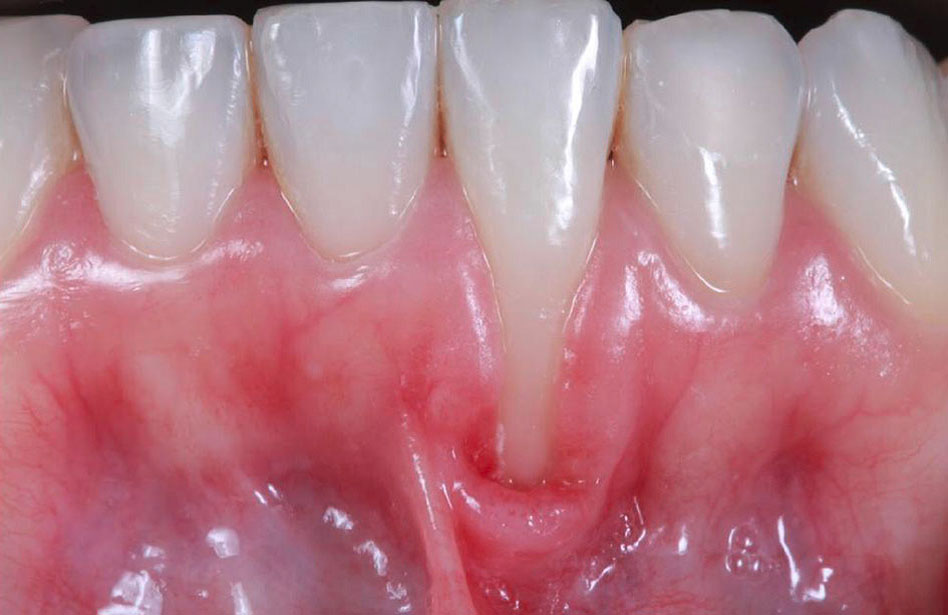

A 26-year-old healthy female patient presented to the private dental office (Rio de Janeiro, Brazil) in May 2019 with a chief complaint of lower root exposure. A full periodontal screening was performed: (probing depth [PD] <4 mm, bleeding on probing [BOP] <10%, and plaque index ≤20%). Upon intraoral examination, a localized recession was noted on tooth #24 (ADA) or #31 (FDI) (lower right central incisor), with 7 mm of buccal recession and 2 mm of width (recession type 1, RT1),11 with no mobility and no interproximal bone loss (Figure 1). There was the absence of local keratinized tissue width (KTW) and the adjacent gingival thickness (GT) less than 1 mm. The goal of the surgical treatment was to reestablish the local gingiva, trying to augment the GT and KTW and prevent further progression of the recession.

Figure 1.

Initial frontal view of the gingival recession at tooth #24.